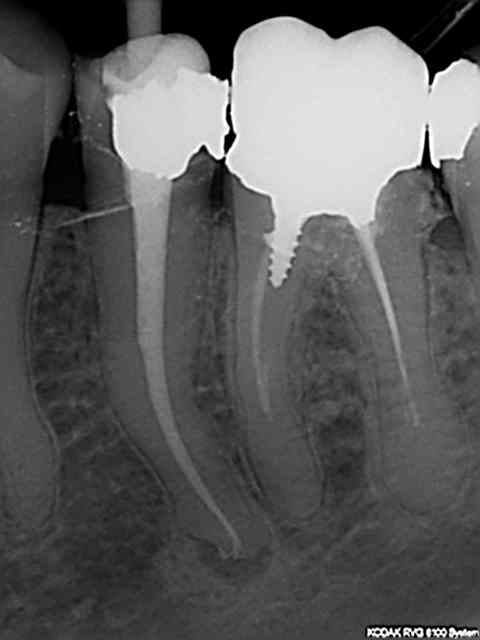

J'utilise d'autres cones je ne sais plus quelle marque mais plus fermes il est vrai. Presque toutes mes endos ressemblent à ca, autant que faire ce peu à mon niveau j'ai trouvé une séquence qui permet d'avoir des résultats reproductibles. Presque car j'ai quelques ratés aussi Genre un instrument de cassé de temps en temps, jamais de fausses routes cependant.

La toile rte du mois quelques fractures instrumentales sur le mv1 (1 puis 2 puis 3) et mv2 récalcitrant.

R2 uvhruy - Eugenol